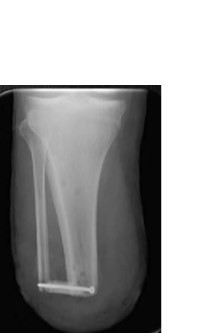

Nos casos de amputação transtibial em membro ISQUÊMICO, quais diferenças na técnica?

A

SEM miodese;

Tíbia mais curta (10cm - 12,5cm);

Flap muscular posterior mais longo (menos vascularização)

Qual a “regra” para definir o tamanho do coto ósseo nos casos não isquêmicos?

30cm altura = 2,5cm coto

Técnica modificada por Etrl et at?

SINOSTOSE TIBIOFIBULAR DISTAL

- Menos lesão na sindesmose

- Coto mais estável